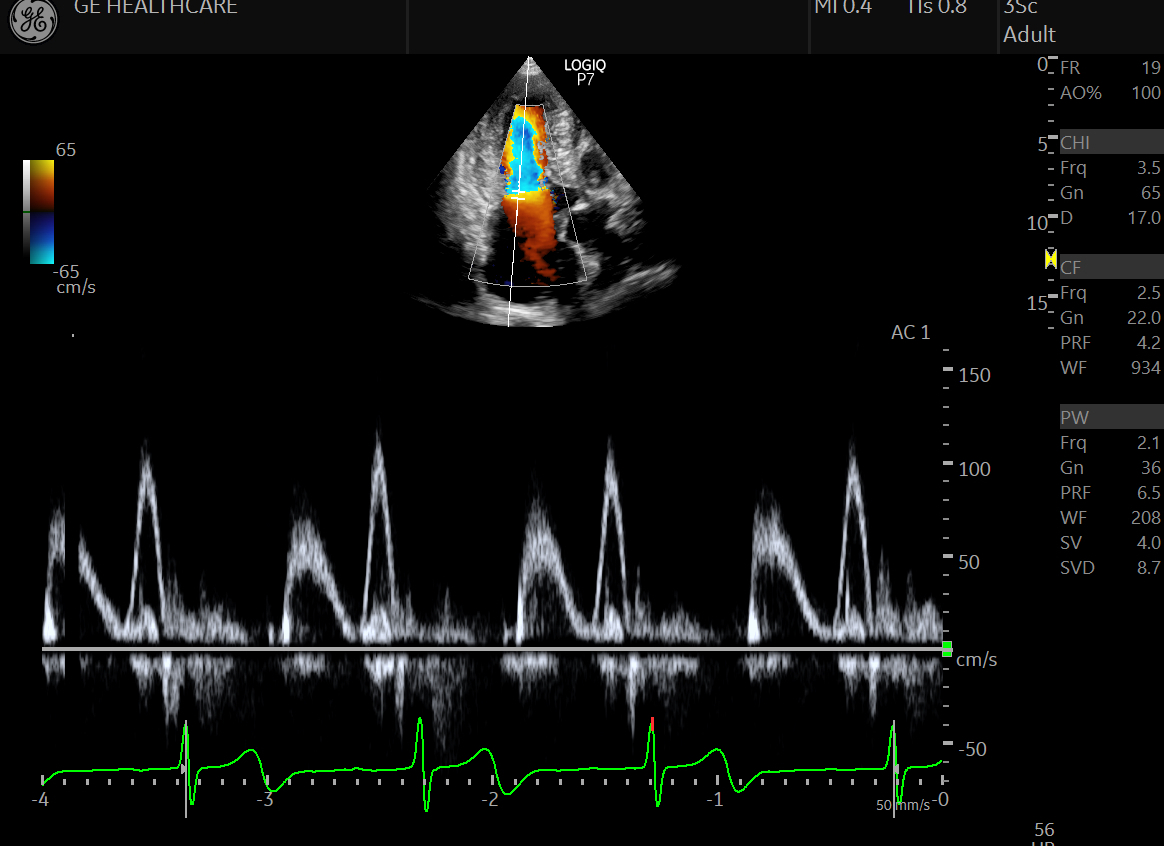

심장 초음파는 초음파를 이용하여 실시간으로 심장의 움직이는 모습을 관찰할 수 있으며, 심장의 해부학적 구조의 이상, 심장 기능, 심장 내 압력 등을 실시간으로, 비침습적으로 관찰할 수 있는 검사법입니다.

경흉부 심초음파, 경식도 심초음파, 운동 부하 심초음파, 도부타민 부하 심초음파, 어고노빈 부하 심초음파, 심근조영 심초음파, 삼차원 심초음파 등 몇 가지 형태로 구분하여 시행됩니다.